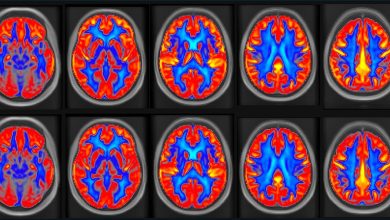

7 Tesla MRI revela como o cérebro humano antecipa e regula as necessidades do corpo

Principais regiões corticais e subcorticais envolvidas na interocepção e alostase. Crédito: Neurociência da Natureza (2025). DOI: 10.1038/s41593-025-02087-x Usando uma tecnologia…

Ler Mais » - Notícias